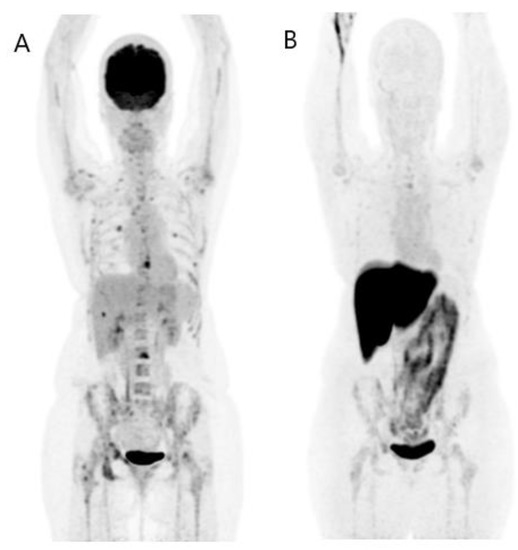

- Kratochwil, C.; Flechsig, P.; Lindner, T.; Abderrahim, L.; Altmann, A.; Mier, W.; Adeberg, S.; Rathke, H.; Röhrich, M.; Winter, H.; et al. 68Ga-FAPI PET/CT: Tracer Uptake in 28 Different Kinds of Cancer. J. Nucl. Med. 2019, 60, 801–805. [Google Scholar] [CrossRef]

- Kömek, H.; Can, C.; Güzel, Y.; Oruç, Z.; Gündoğan, C.; Yildirim, Ö.A.; Kaplan, İ.; Erdur, E.; Yıldırım, M.S.; Çakabay, B. 68Ga-FAPI-04 PET/CT, a new step in breast cancer imaging: A comparative pilot study with the 18F-FDG PET/CT. Ann. Nucl. Med. 2021, 35, 744–752. [Google Scholar] [CrossRef]

- Hu, K.; Wang, L.; Wu, H.; Huang, S.; Tian, Y.; Wang, Q.; Xiao, C.; Han, Y.; Tang, G. [18F]FAPI-42 PET imaging in cancer patients: Optimal acquisition time, biodistribution, and comparison with [68Ga]Ga-FAPI-Eur. J. Nucl. Med. Mol. Imaging 2022, 49, 2833–2843. [Google Scholar] [CrossRef]